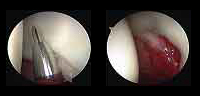

La artroscopia proporciona una forma poco agresiva para tratar los problemas dentro de la articulación con un menor daño a los tejidos y una recuperación más rápida y confortable.

- ¿Qué es la artroscopia de cadera?

La artroscopia es un procedimiento quirúrgico que permite estudiar, diagnosticar y tratar problemas en una articulación. Consiste en la introducción por punción, en este caso dentro de la cadera, de un sistema óptico con fuente de luz conectado a una cámara digital que permite visualizar las estructuras intraarticulares. - ¿Cuáles son las lesiones más frecuentes que trata la artroscopia de cadera?